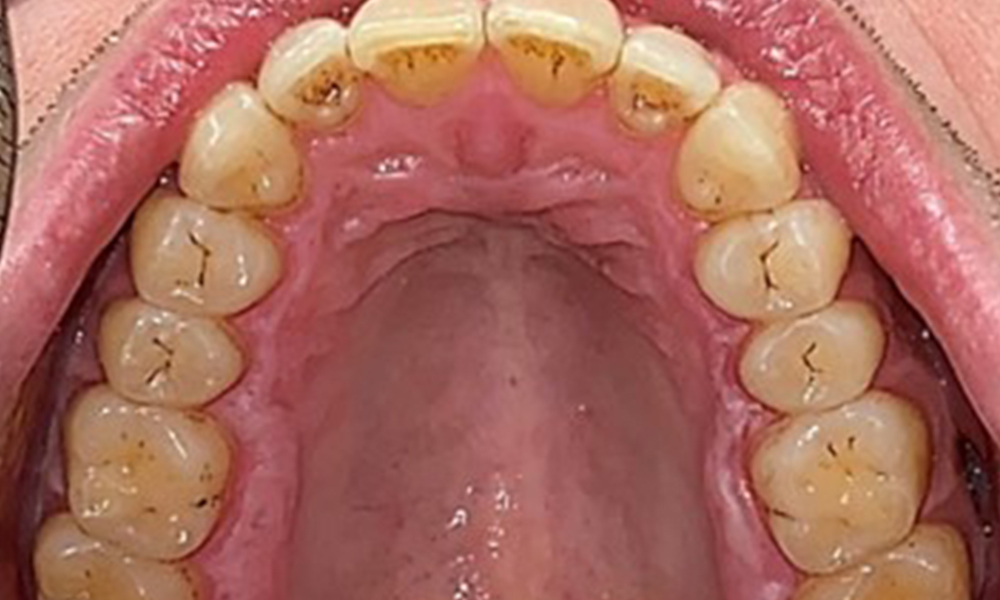

Occlusal view of the maxilla, © Dr R. Krapf

Fig. 3: Occlusal view of the maxilla, © Dr R. Krapf

There were no pathological extraoral findings. During intraoral examination, inspection of the frontal view revealed brownish discolouration near the keratinised gingiva and at the transition to the moveable mucosa (Fig. 2), which could be attributed to nicotine consumption. Whitish mucosal lesions were observed on the palate, particularly near the maxillary molar palatal surfaces, indicating increased keratinisation and can also be attributed to nicotine consumption. The tongue was covered with a removable white and brownish coating.

The patient has full dentition with a total of 28 teeth. There were noteworthy erosions and attritions. (Fig. 4, Fig. 5). Due to bruxism, the patient has been wearing a splint with an adjusted bite block at night for many years. The erosions were caused by long-term consumption of isotonic beverages. No periodontal bone loss or active caries were observed.